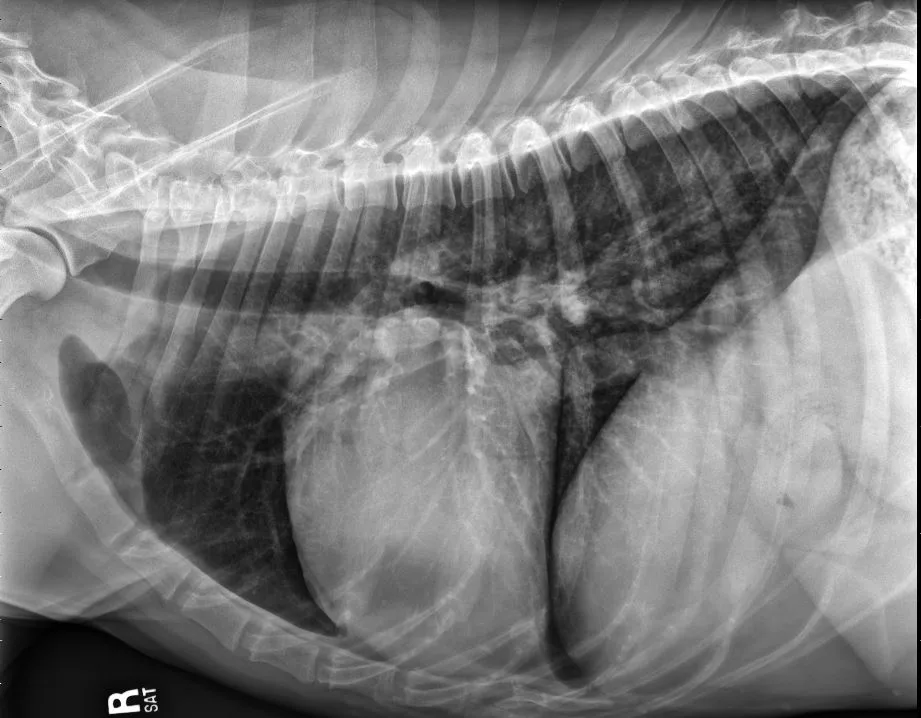

FIGURE 11 Right lateral (left) and VD (right) projections of a crossbreed dog with tricuspid valve dysplasia. The cardiac silhouette has increased width, and the regions of the right atrium and ventricle show roundness. The cardiac apex is displaced to the left secondary to right-sided enlargement (right). The caudal vena cava (arrowheads) is dilated, and there is loss of abdominal serosal detail secondary to increased systemic venous pressures and right-sided CHF, respectively. The pulmonary vasculature is small secondary to pulmonary hypoperfusion (given significant regurgitation across the tricuspid valve and decreased forward blood flow). VHS, VLAS, M-VLAS, and VRHi collected from the right lateral view are 12.3, 2.3, 2.7, and 3.8, respectively. Images courtesy of Bruna Del Nero, DACVIM (Cardiology)